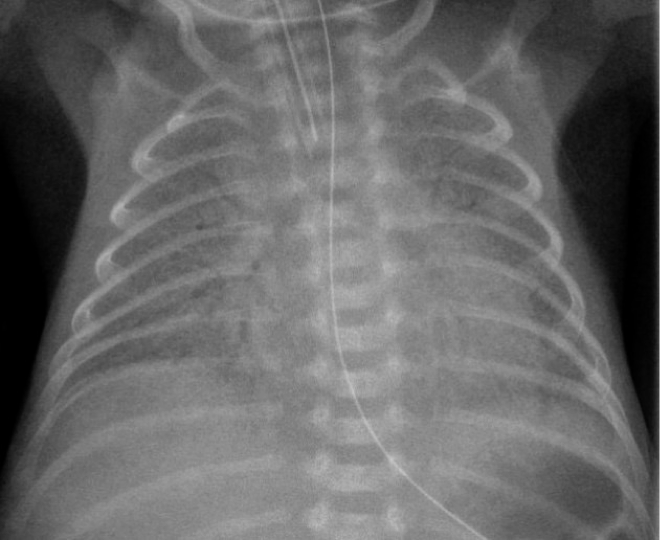

Radiographic Findings

1 or 2 = RDS

- Low lung volume

- Air bronchogram

- Diffuse fine atelectasis (ground glass appearance)

- Near-total atelectasis will show complete opacification of lungs (White Lung)

Chest radiographs: Bilateral, diffuse, reticular granular, or ground glass appearances; air bronchograms (prominent air bronchograms represent aerated bronchioles superimposed on a background of collapsed alveoli); poor lung expansion.